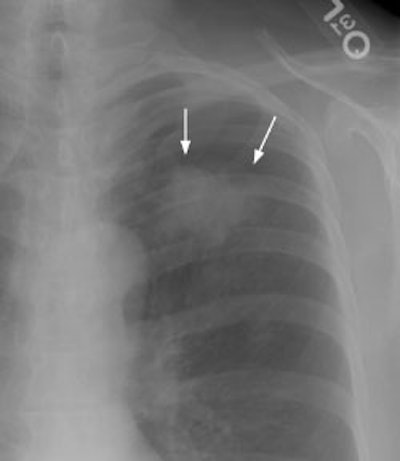

New Criterion for Determination of Pathologic Hilar Adenopathy

Example 1: This is an example of an N1 node in a patient with a lingular adenocarcinoma (left image). Although not pathologic by short axis size criteria, the lymphatic tissue in the left hilum has a convex border with the adjacent lung (white arrows). This node contained adenocarcinoma at histopathologic analysis. Some authors advocate using the presence of a convex margin of the interstitium with the lung parenchyma to indicate pathologic adenopathy to improve the sensitivity of CT for detecting hilar metastases [36].

NOTE: Click image to enlarge